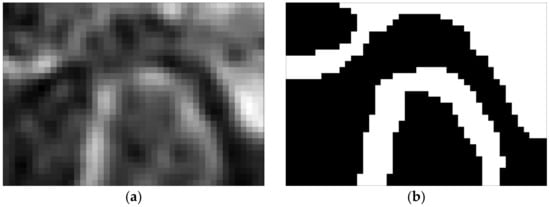

3.1. TMJ Head Segmentation and πV Slice

An exemplary set of axial slices images is presented in Figure 9. The slices are limited to VOI and constitute the input for further processing. The results of the TMJ head segmentation are visible in Figure 10. The head of the joint has been properly segmented. The shape of the head is a little bit thicker than might be expected looking at the source images. It is caused by approximating the head by its convex hull. However, the approximation does not influence the determination of the , as the length of the TMJ head remains unchanged. For each of the shapes, the minimum area rectangle is determined and the longest section connecting the points lying on the opposite sides of the rectangle is calculated. For that, the sets of common pixels between the shorter sides of the rectangle and the TMJ head shape are found. Then, all possible sections connecting the points are determined. The coordinates of the ends of the longest ones are remembered for further processing. The process is repeated for each segmented axial slice section of the TMJ head. The ends of the sections are used for determining the direction of the plane. The plane is vertical and crosses the mid-point of the projection of the section connecting the innermost and the outermost voxel identified during the axial slices analysis.

Figure 10.

The slices containing the TMJ head segmented from the slices presented in Figure 9. The first pictures are black, as no part of the TMJ head was present on them.

This plane creates a certain angle with the y axis of the coordinate system. Knowing the position of the said section, one can easily find this angle. Determining the cross-section given by this plane requires finding of all the voxels it cuts through and interpolating their values. In practice, it turned out to be more convenient to rotate the entire scan by this angle so that the plane becomes parallel to one of the planes of the coordinate system. The reference cross-section obtained in this way is shown in Figure 11.

Figure 11.

Reference slice used for the determination of TMJ parameters: (a) slice taken in πV plane and (b) slice segmentation.